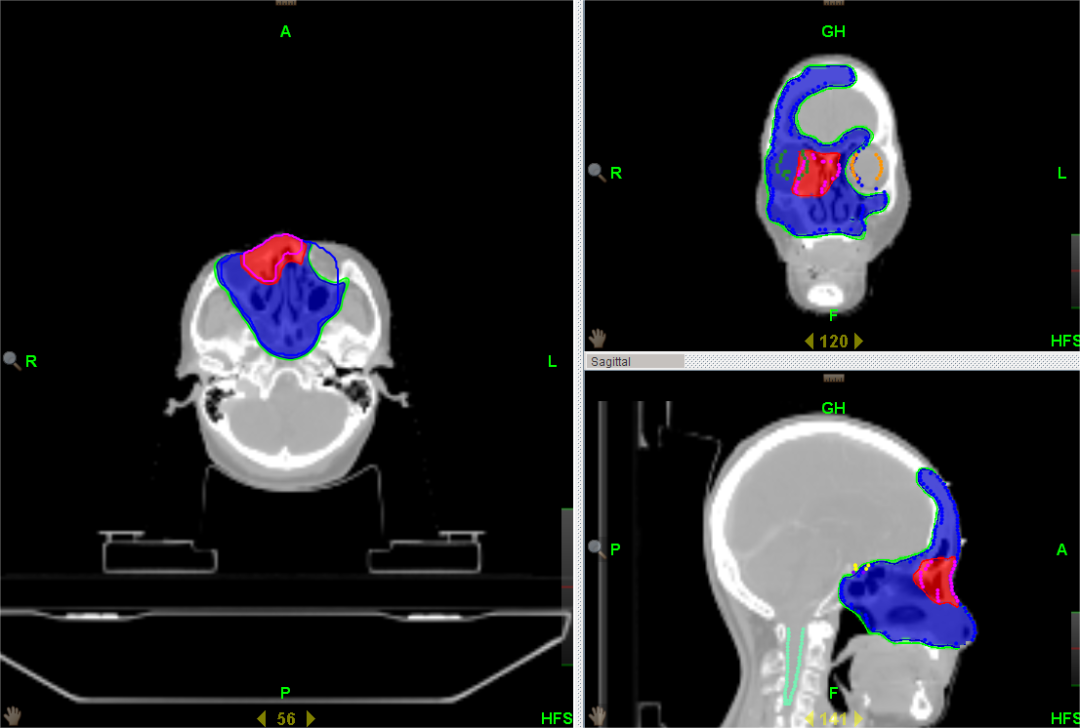

为了让“我”的优点发挥的更加明显,让更多的患者能够在“我”的治疗下得到痊愈。湘南学院附属医院引进的TomoTherapy(简称TOMO)——螺旋断层放疗系统,属于最新一代放射治疗设备。是目前唯一采用放疗照射与CT同源的影像引导放疗系统。成像精度高达±0.1mm,远远高于常规加速器。

与普通的“我”相比,TOMO放疗有以下优势:

1、对全身多发病灶及病变较长的大肿瘤,超出普通加速器治疗所能达到的范围,常规放疗往往不能同时包括,TOMO能够实现连续同时完成照射。包括易通过淋巴转移产生多病灶的恶性肿瘤、全脑全脊髓和全身骨髓调强照射等。

2、对解剖结构复杂等难治性、特殊的恶性肿瘤更具优势。包括鼻咽部肿瘤、全颅骨放疗、头皮恶性肿瘤、胸壁恶性肿瘤等。

3、对紧邻重要脏器或组织的恶性肿瘤,如肿瘤紧邻肝、肾、肺、鼻咽、前列腺等重要器官时,由于这些脏器对射线敏感,往往制约常规放疗放射剂量的提高,TOMO能够避开重要器官,降低副反应的同时提高放射剂量,使得既往不易放疗的患者变为可以放疗。